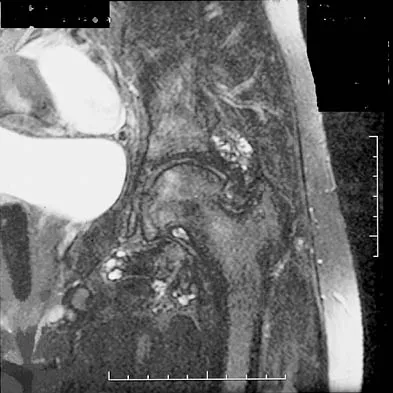

A 31-year-old woman has increasing pain and tightness in her right knee, with occasional stiffness and recurrent hemorrhagic effusions. MRI scans are shown in Figures 2a and 2b. What is the most likely diagnosis?

PVNS is a rare inflammatory granulomatous condition of unknown etiology, and causes proliferation of the synovium of joints, tendon sheaths, or bursa. The disorder occurs most commonly in the third and fourth decades but can occur at any age. MRI provides excellent delineation of the synovial disease. Characteristic features of PVNS on MRI include the presence of intra-articular nodular masses of low signal intensity on T1- and T2-weighted images and proton density-weighted images. Synovial biopsy should be performed if there is any doubt of the diagnosis. Total synovectomy (open or arthroscopic) is required for the diffuse form, although recurrence is common. Rheumatoid arthritis and synovial chondromatosis are not typically associated with hemorrhagic effusions. De Ponti A, Sansone V, Malchere M: Result of arthroscopic treatment of pigmented villonodular synovitis of the knee. Arthroscopy 2003;19:602-607. Chin KR, Barr SJ, Winalski C, et al: Treatment of advanced primary and recurrent diffuse pigmented villonodular synovitis of the knee. J Bone Joint Surg Am 2002;84:2192-2202.